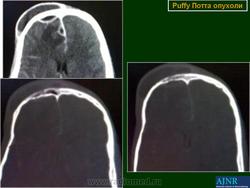

Описанная впервые сэром Персивалем Поттом в 1760 году, "одутловатая" опухоль представляет собой тестообразное вздутие на лбу, вызванное эрозией передней стенки пазухи, как последствие остеомиелита лобной пазухи. Инфекционное воспаление кости может произойти непосредственно или чаще всего из-за тромбофлебита диплоических вен, в результате которого происходит инфицирование костного мозга. Чаще всего в процесс вовлекается лобная кость. Осложнения, как правило, наблюдаются у подростков и молодых людей, возможно, в связи с тем, что у них диплоические вены наиболее развиты. Основной возбудитель инфекции - Staphyloccocus aureus. Радиография выявляет участок кости, будто выеденный молью. На ранней стадии болезни, однако, результаты рентгенографии или компьютерной томографии бывают нормальными.

7. Опухоль Потта представляет собой субпериостальный абсцесс лобной кости. Является осложнением воспалительного процесса в лобной пазухе. Часто сочетается с развитием эпидурального абсцесса. Лечение хирургическое - санация лобной пазухи наружным, реже - внутриносовым доступом с удалением кариозно измененной кости в сочетании с антибиотикотерапией.